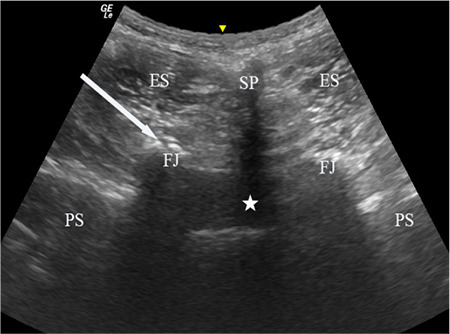

Abstract Image